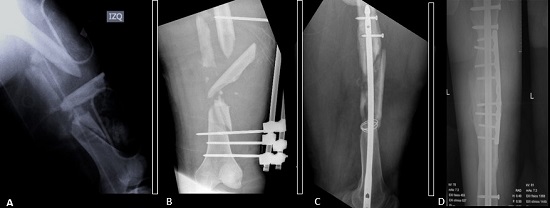

The definitive stabilization of long bone fractures in the first 24 hours positively impacts survival1,21-23. Hemodynamically stable patients should undergo definitive fixation of fractures during the first surgery (Figura 3). However, prolonged interventions (over 90 minutes) in hemodynamically unstable patients are associated with unfavorable outcomes. Furthermore, major surgery can trigger and increase immune response resulting in a clinical condition called “Second Trauma” 15,17,24. Therefore, delayed definitive stabilization has been implemented in hemodynamically unstable patients to reduce the effect of the second trauma 25,26. These patients should undergo damage control with a temporary fixation, followed by physiologic stabilization and a deferred definitive fixation in a second surgical time 5 to 10 days after damage control (Figura 4) 10,16,27,28.